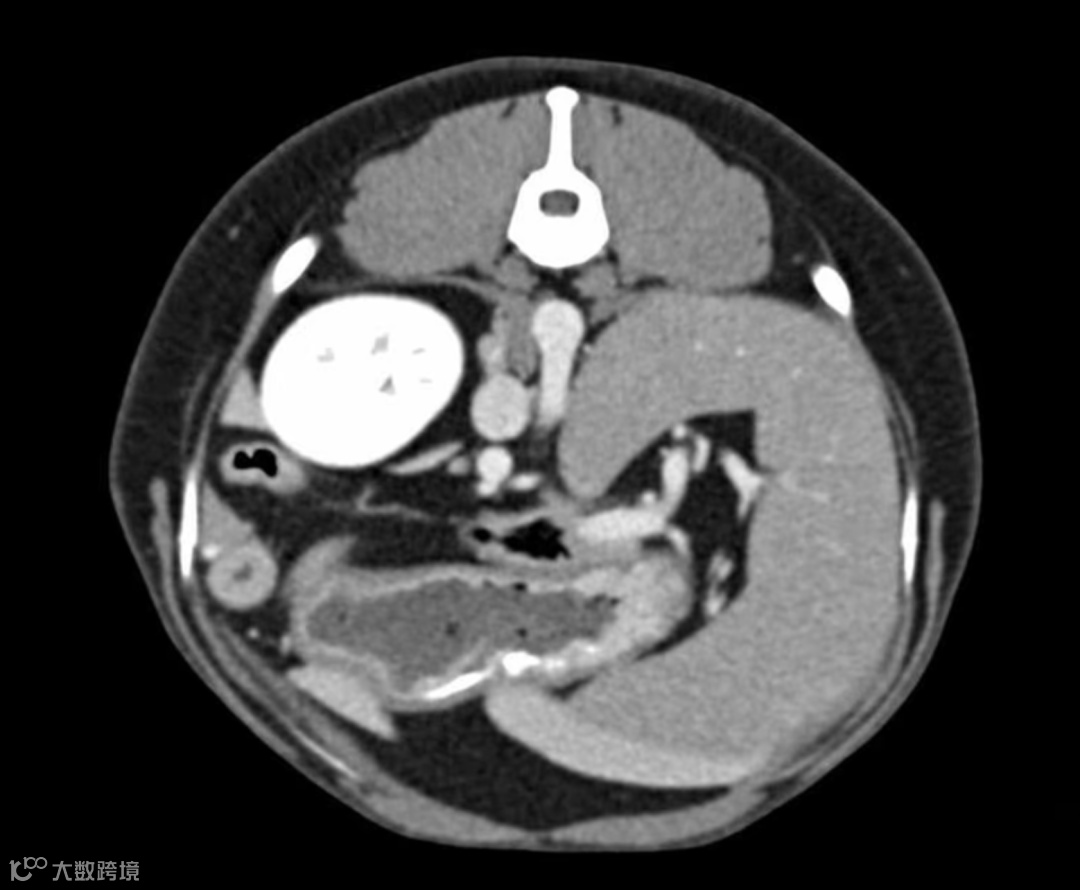

三位重建显示骨盆骨折:

可以看出,小动物除了在做检查的时候比人类困难😅,诊断难度好像没有高很多?